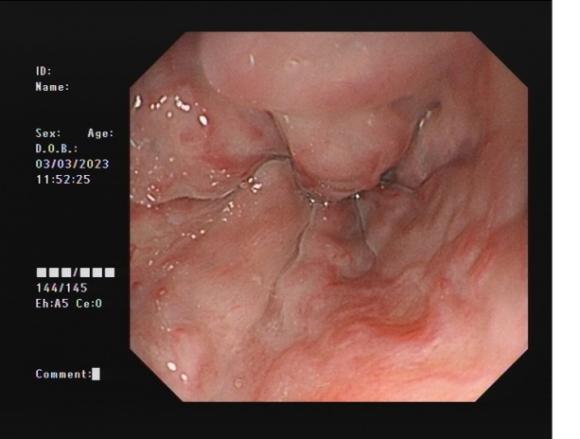

食管靜脈曲張 內鏡下套扎術

食管靜脈曲張套扎術(EVL):治療食管靜脈曲張、胃底靜脈曲張破裂出血、藥物止血無效者;既往有食管靜脈曲張破裂出血史者預防再出血。